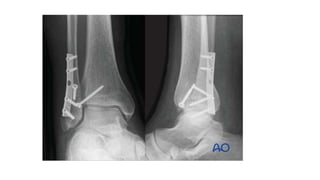

Buttress/Antiglide plate • “holds”the bone up • A buttress is a construction that resists axial load by applyingforce at 90° to the axis of potential deformity. • When used in intraarticular fractures- buttress • When used in diaphyseal fractures- antiglide • The plates are usually precontoured according to the shape